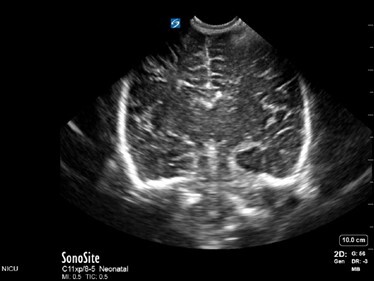

Neonatology Normal Anatomy 1 Image